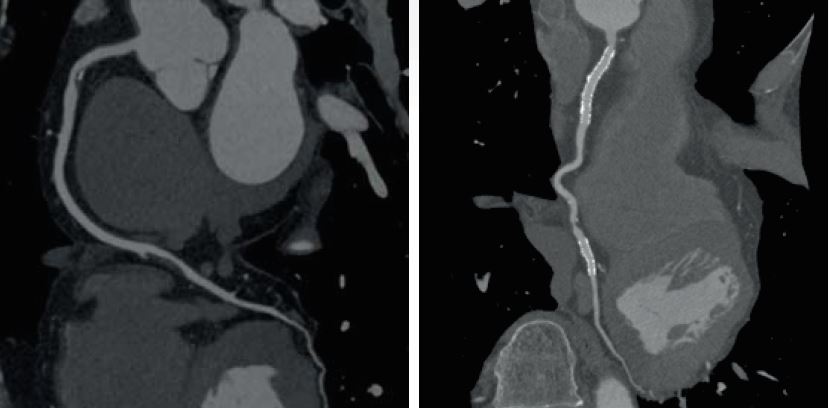

Ultra-High Resolution CT

Чітка візуалізація коронарних стентів та детальне окреслення бляшок за допомогою КТ із надвисокою роздільною здатністю. Aquilion Precision — це перший у світі КТ, здатний розпізнавати анатомічні деталі розміром до 150 мікрон, забезпечуючи якість КТ- зображень із роздільною здатністю, яка зазвичай спостерігається лише на ангіографічному обладнанні.

• Оцінювати складну патологію з кальцифікатами та встановлювати стент за допомогою ультрависокої роздільної здатності Aquilion Precision.